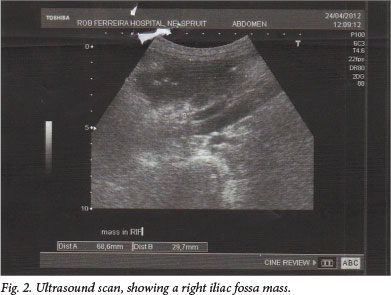

An ultrasound scan on 24 April 2012 at RFH revealed a large mass of para-aortic lymph nodes, with a poorly circumscribed RIF mass of 69 x 30 mm (Fig. 2). The liver and spleen were normal and no renal calculi were seen. The gynaecology team ruled out pelvic inflammatory disease. The Surgery Unit requested a computed tomography (CT) scan of the abdomen and a sputum specimen for tuberculosis (TB) diagnosis (no record of the latter could, however, be found).